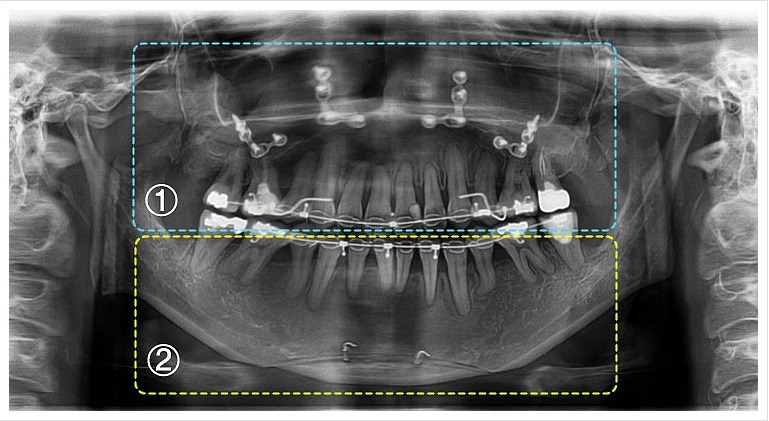

양악수술은 여러 단계로 이루어집니다. 먼저, 환자의 상태를 진단하기 위해 X-ray 촬영과 3D 스캔을 진행합니다. 이후, 수술 계획을 세우고, 수술 당일에는 전신 마취를 시행합니다. 수술 과정은 상악과 하악의 뼈를 절단하고, 필요한 위치로 이동시킨 후 고정하는 방식으로 진행됩니다. 수술 시간은 보통 1~7시간 정도 소요됩니다.

| 양악수술 전 (정면) | 양악수술 후 (정면) |